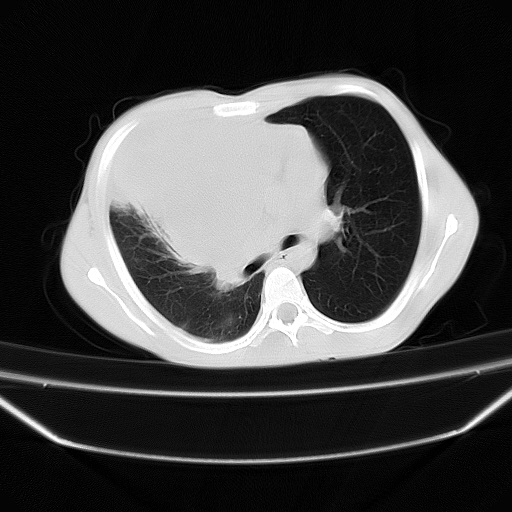

以下是引用zjzjr在2008-7-20 12:57:00的发言:[br]考虑为生殖源性肿瘤(内胚窦瘤),侵袭性胸腺瘤可能性大;右侧少量胸腔积液。

以下是引用xinliheng001在2008-7-20 21:17:00的发言:[br]右纵隔巨大分叶状软组织均质密度肿块,右上肺叶受压明显,纵隔右移、胸膜受累有少量积液和结节样增厚。应增强扫描一定会有更具诊断价值的信息。

以下是引用xinliheng001在2008-7-20 21:17:00的发言:[br]右纵隔巨大分叶状软组织均质密度肿块,右上肺叶受压明显,纵隔右移、胸膜受累有少量积液和结节样增厚。应增强扫描一定会有更具诊断价值的信息。